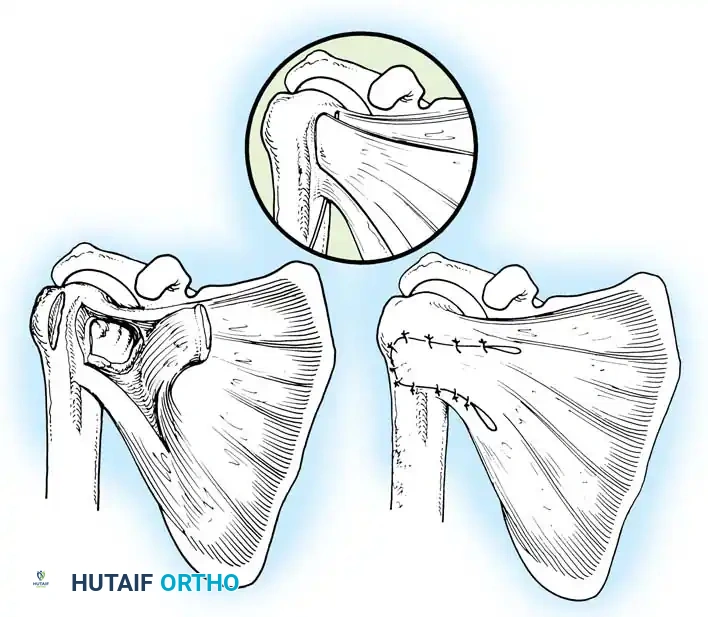

The Bankart Lesion and Capsular Failure

In 1906, Perthes first described the detachment of the anteroinferior labrum. In 1938, Bankart popularized the concept, describing the traumatic detachment of the fibrocartilaginous labrum and anterior capsule from the glenoid rim—now universally known as the Bankart lesion. Rowe et al. identified Bankart lesions in 85% of traumatic recurrent dislocations.

Bipolar Bone Loss

A Hill-Sachs lesion is an impaction fracture of the posterolateral humeral head, created when the head is driven against the hard anterior glenoid rim during dislocation. Burkhart and DeBeer introduced the concept of the "engaging" Hill-Sachs lesion, which levers the humeral head out of the joint when the arm is abducted and externally rotated.

Concurrently, anterior glenoid rim fractures or attritional bone loss can occur. Itoi demonstrated that a 20% loss of the anterior glenoid width critically compromises stability, rendering soft-tissue repairs (like an isolated Bankart repair) biomechanically insufficient. Advanced imaging (3D CT or MRI arthrography) is mandatory to quantify bone loss.

Glenoid Preparation and Labral Repair

The essential step in restoring stability is the anatomical reduction of the capsulolabral complex to a bleeding bone bed on the anterior glenoid rim.

- Debridement: The anterior glenoid neck is decorticated using a motorized burr, rasp, or osteotome to create a bleeding cancellous bed. This promotes robust biological healing of the repaired labrum.

- Mobilization: The scarred, medially displaced labrum (ALPSA lesion) must be fully mobilized using a periosteal elevator until the subscapularis muscle belly is visible anteriorly. The tissue must float freely to be shifted superiorly and laterally.

- Anchor Placement: Suture anchors (typically 3 to 4) are placed along the articular margin of the anteroinferior glenoid (from the 5:30 to 3:00 positions for a right shoulder). Anchors must be inserted at a 45-degree angle to the articular surface to maximize pullout strength and avoid joint penetration.